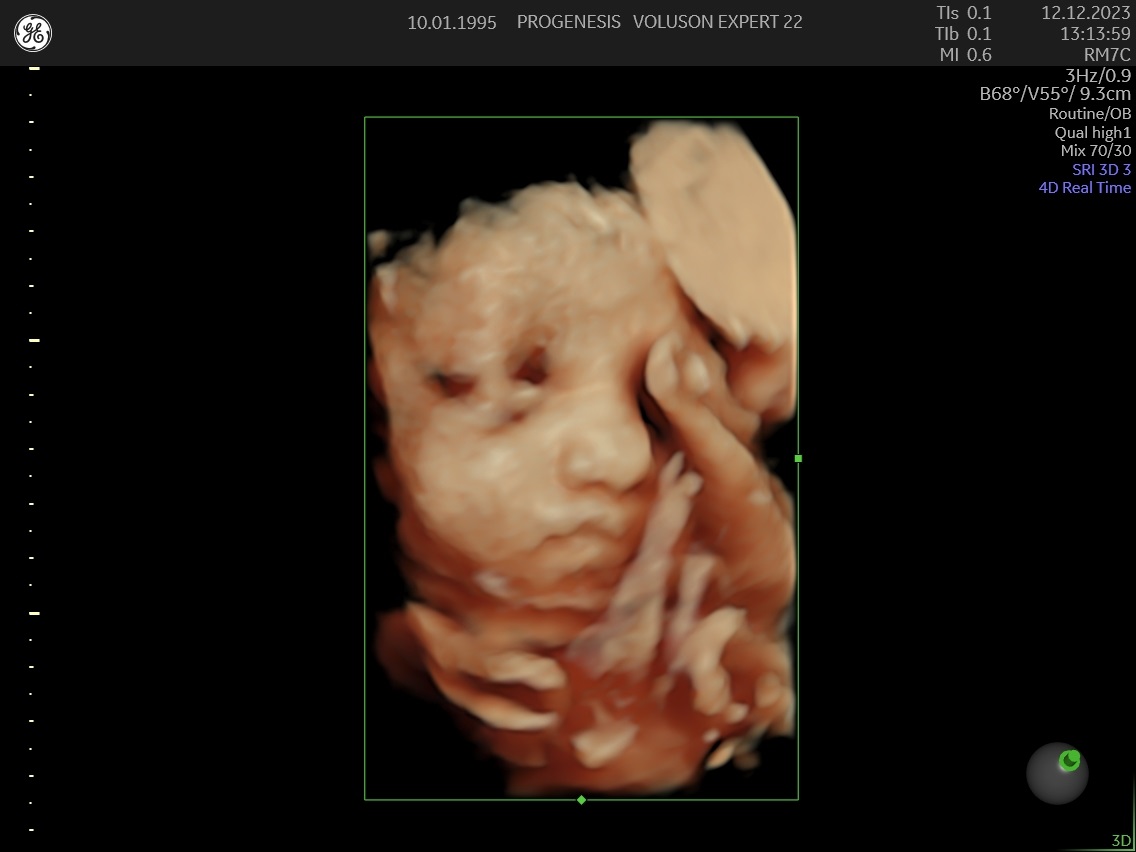

3D/4D LIVE Υπερηχογράφημα

Το 3D/4D LIVE είναι μια νέα τεχνολογία υπερήχων που δημιουργεί εικόνες του εμβρύου σε τρισδιάστατο ή τετραδιάστατο χώρο. Οι εικόνες αυτές είναι πιο ρεαλιστικές από τις παραδοσιακές εικόνες υπερήχων και δίνουν στους γονείς μια πιο ολοκληρωμένη εικόνα του μωρού τους.

Σε πιθανά ανατομικά προβλήματα του εμβρύου μπορούν να βοηθήσουν στην κατανόησή τους από τους γονείς.

Ωστόσο, οι εικόνες 3D/4D LIVE δεν μπορούν να αντικαταστήσουν τις παραδοσιακές εξετάσεις υπερήχων.